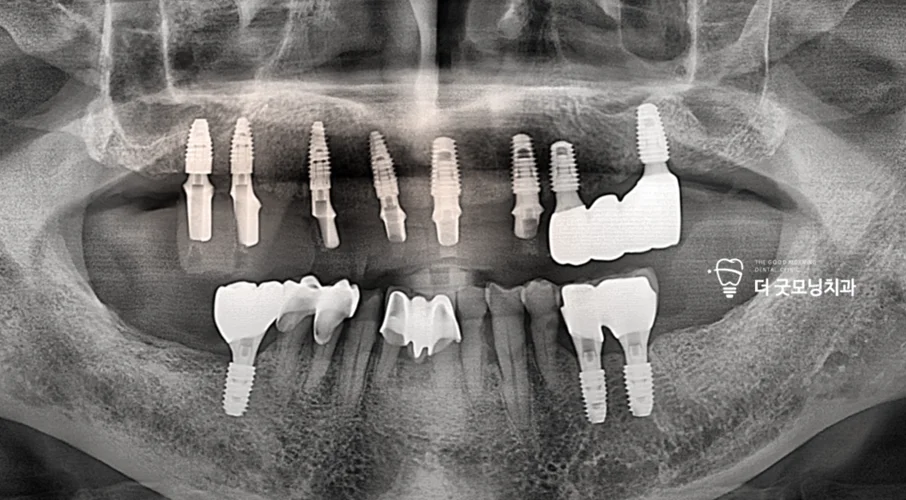

Step 1. 초진 상태 확인

초진 시 여러 치아가 이미 상실된 상태였으며, 하악에 남아있던 어금니 2개는 심한 충치로 보존이 불가능한 상태였습니다. 우측 상악에는 브릿지가 씌워져 있었으나 지대치의 이차 우식 및 파절이 진행되어 잔존치 발치가 필요한 상황이었습니다.